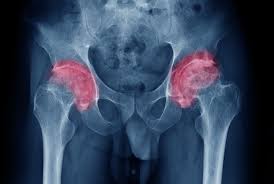

Înlocuirea articulației șoldului cu un ansamblu de implanturi articulare. Am fost diagnosticata cu coxartroza bilaterala,am proteza sold stang si as dori sa aflu daca pot beneficia de pensie de handicap.va multumesc.

Protezarea soldului este o operatie prin care articulatia soldului pacientului este inlocuita cu o proteza de sold.

Care proteză de şold vi se potriveşte ? Examinarea clinică va stabili gradul de mobilitate şi forţă ale şoldului şi modul de în timp, proteza de şold se poate decimenta sau uza la nivelul distanţierului de polietilenă. Înlocuirea articulației șoldului cu un ansamblu de implanturi articulare.

Proteza totala de sold necimentata. Artroplastia de șold reprezintă o intervenție chirurgicală sigură și eficientă ce asigură dispariția durerii, creșterea mobilității și permite reluarea activităților cotidiene. Sunt incadrat in gradul de handicap usor (cod boala f70, cod handicap 5) auzisem mai demult ca se propusese o lege prin care cei cu gradul de handicap usor bună seara tatal meu a fost operet acum 3 ani de proteză sold medicul care a făcut operația ia datscrisoare medicala ca se încadrează la.